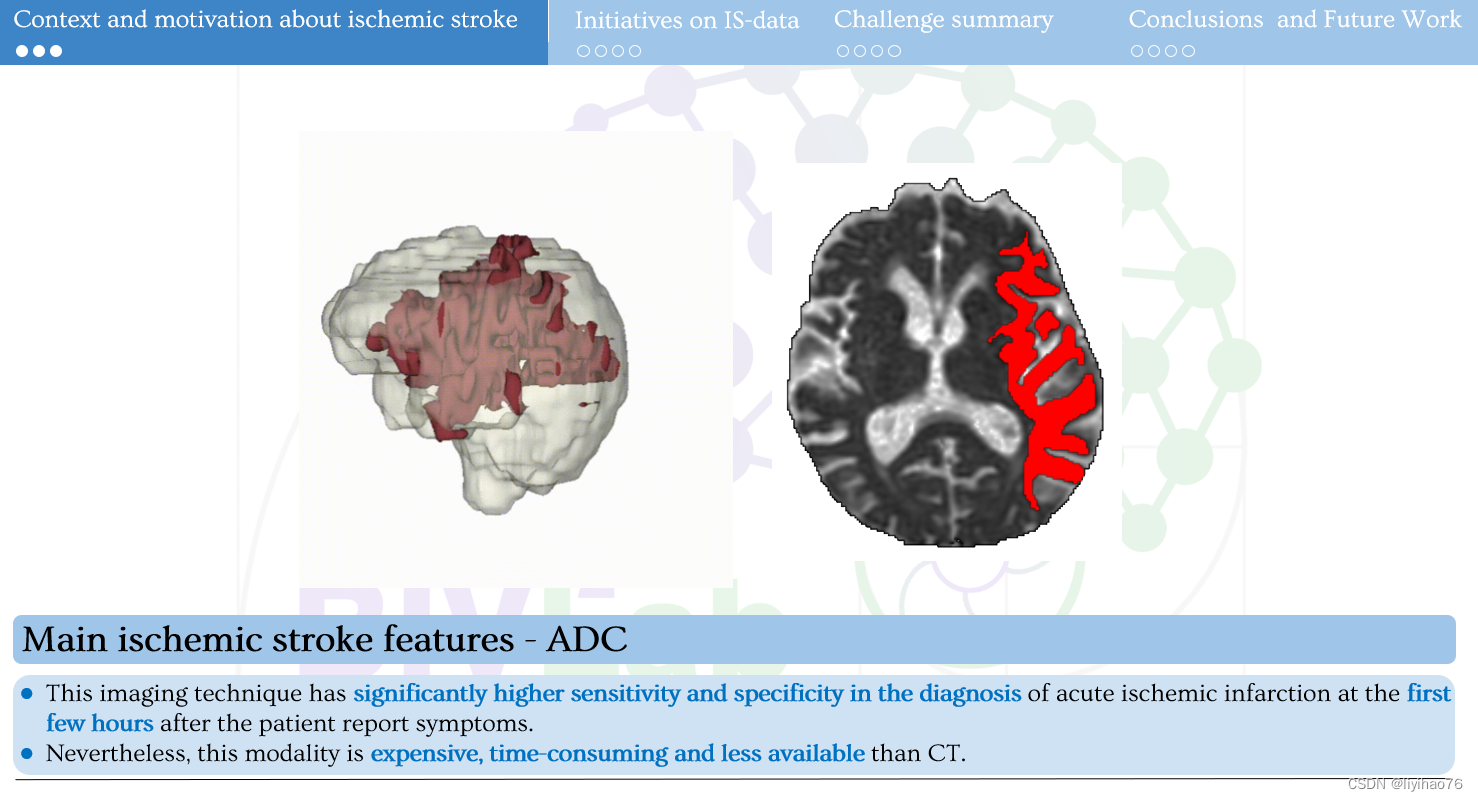

中风是全球第二大死亡原因。 即时诊断的关键组成部分是定位(通过 CT 扫描)和病变描绘(通过 MRI 研究)。 尽管如此,病灶的描绘仍然很差,仅在晚期可见,并且分析使用手动描绘。 这个挑战引入了 CT 和 ADC 研究的配对数据集。 邀请研究人员提出计算策略,在训练期间处理配对数据,并处理 CT 起始序列上的病变分割。 在培训期间,将提供带注释的配对序列(来自一位专家),并且将针对两位专家比较用于测试的结果分割。

CT (NCCT) 主要允许对中风和其他病理进行分类。 然而,此类序列对缺血的对比度差、敏感性和特异性低,并且病变的低衰减具有时间依赖性。因此,临床方案包括扩散加权 MRI 序列,例如 ADC(表观扩散系数),以正确描述和量化中风病变,除其他外,允许正确显示缺血半影和缺血核心。APIS 挑战赛提供配对 (CT-ADC) 数据集。 有 60 个成对的 (CT-ADC) 数据集以及来自专业放射科医师的相关描述以供训练。 最后将使用40个数据集作为测试集进行验证

- ADC

-这种成像技术在患者报告症状后的最初几个小时诊断急性缺血性梗死具有显着更高的敏感性和特异性。

-然而,这种方式比 CT 昂贵、耗时且可用性低。